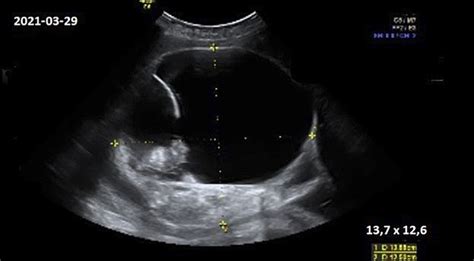

Iš karto po placentos atsidalijimo gimda susitraukia ir įgauna apvalią formą. Po gimdymo ji sveria apie 1 kilogramą. Praėjus savaitei, šis svoris sumažėja perpus ir lieka tik 500 gramų. Pogimdyvinio laikotarpio pabaigoje gimda atgauna prieš nėštumą buvusį dydį ir svorį - apie 50 gramų.